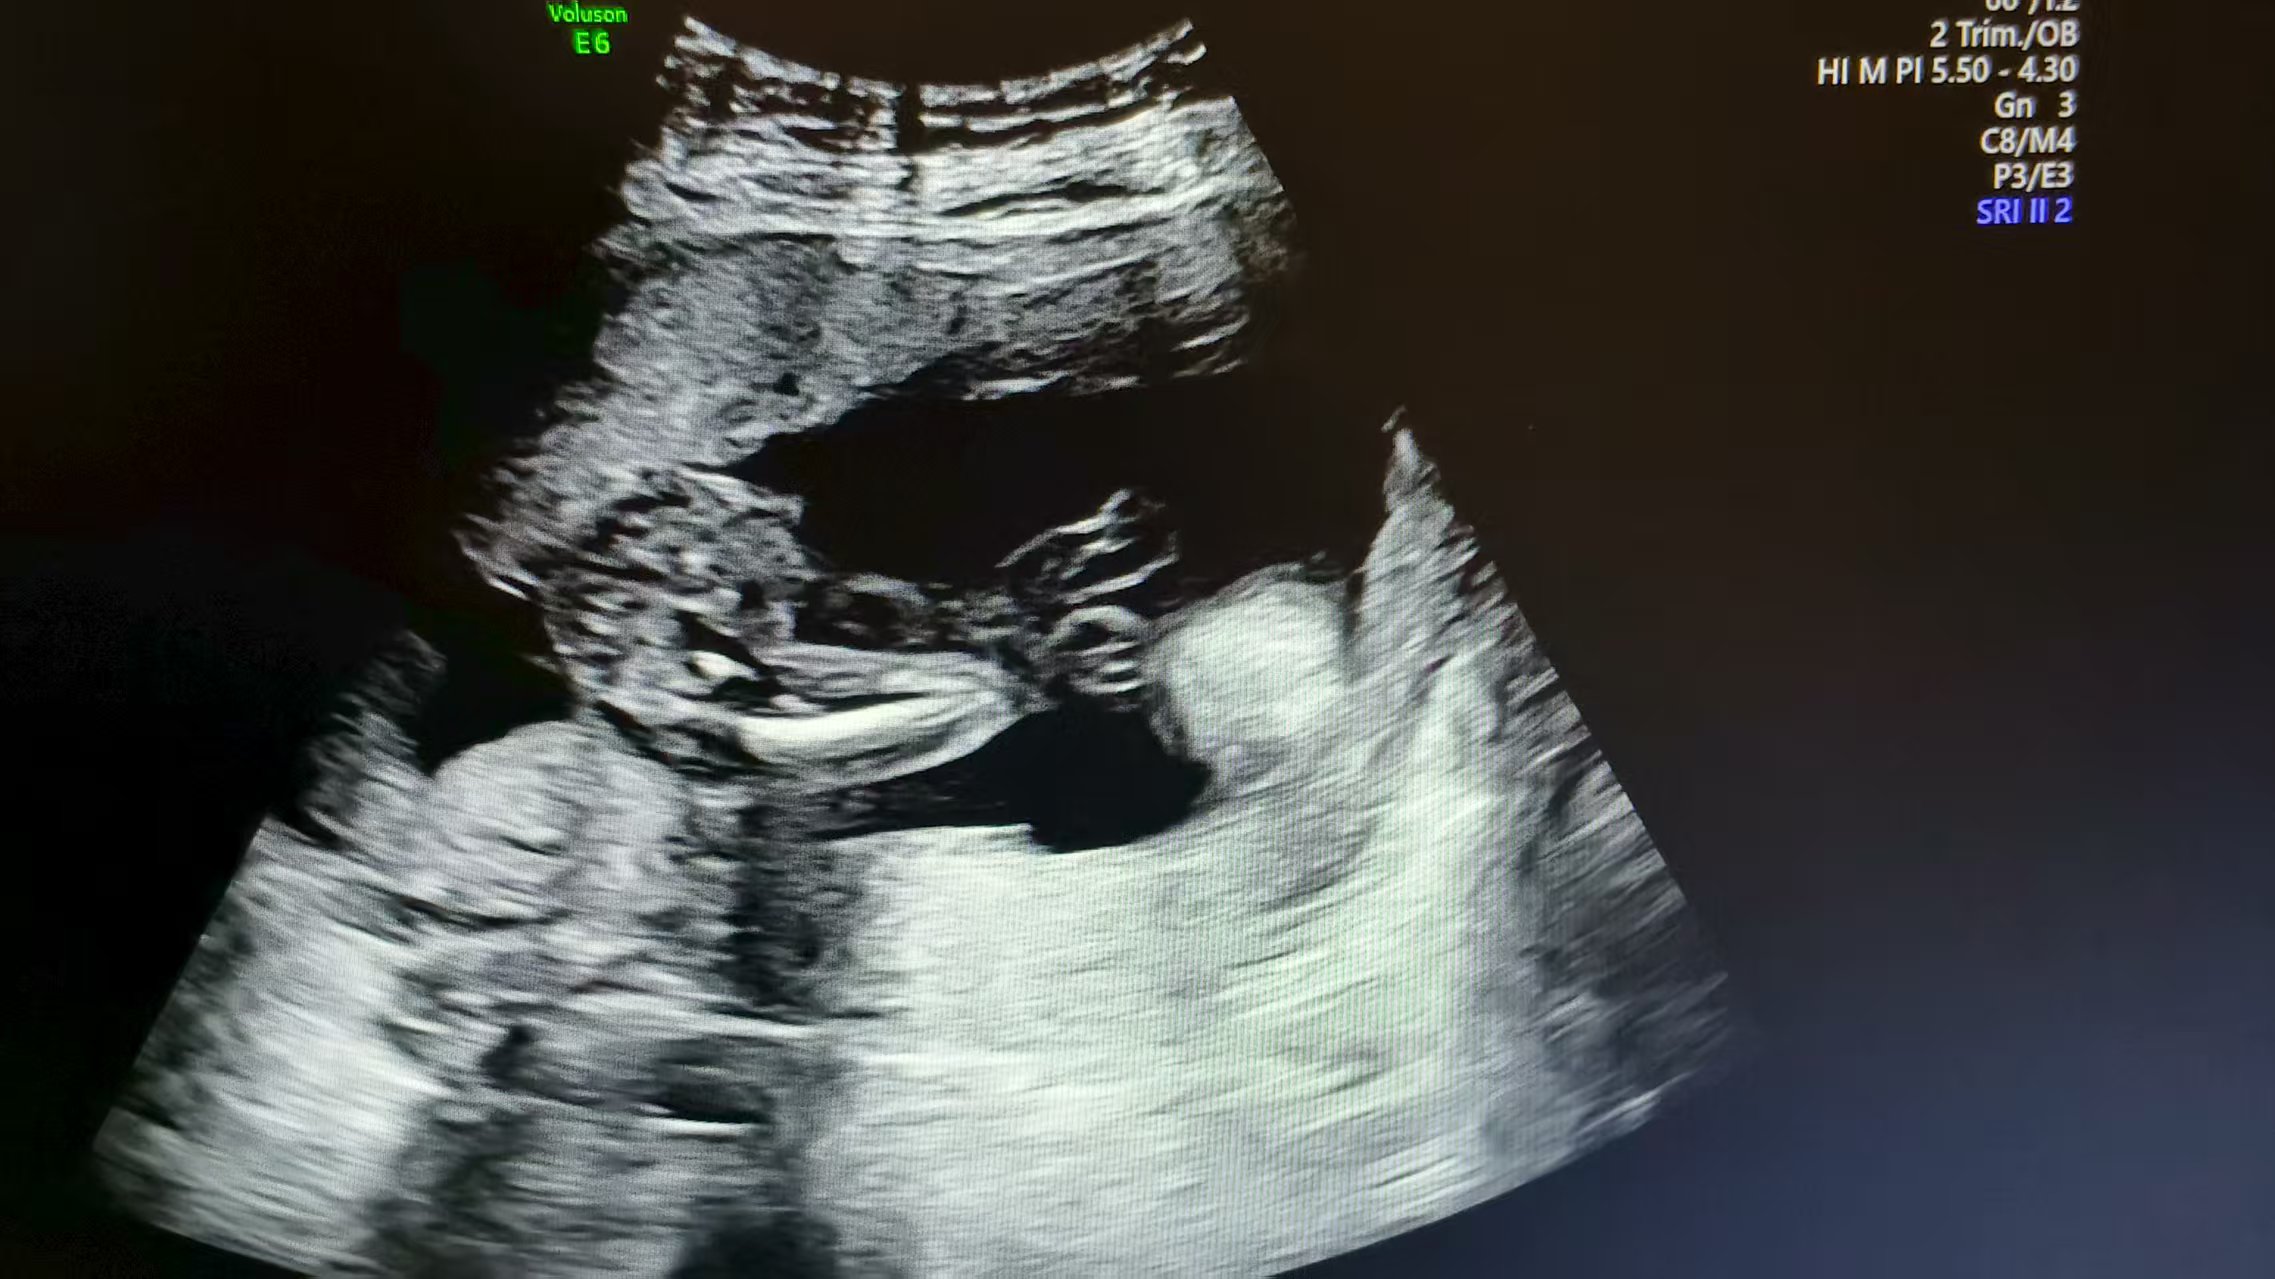

· 陣元問(wèn)題:探頭的陣元長(zhǎng)期使用后會(huì)有衰減,甚至完全損壞,當(dāng)相鄰的多個(gè)陣元損壞時(shí),會(huì)形成暗道或倒三角黑區(qū),使整體圖象回聲強(qiáng)度偏低。對(duì)于損壞的陣元,需要專業(yè)人員使用專業(yè)工具和設(shè)備進(jìn)行更換。